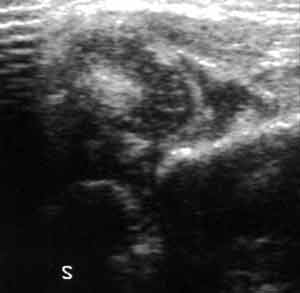

Ультразвуковая диагностика дисплазии тазобедренных суставов.

Рис. 7. Ультразвуковое изображение (Слева) и схема (Справа) подвывиха сустава. Головка бедренной кости расположена эксцентрично. При подвывихе и вывихе бедра угол альфа < 43о, а угол бетта > 77о.